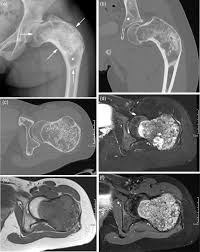

Enchondromas have a characteristic appearance on Magnetic Resonance Imaging MRI as well. Oral Surgery Oral Medicine Oral Pathology Oral Radiology is required for all clinicians involved in the diagnosis and treatment of oral and maxillofacial disease. GeneReviews an international point-of-care resource for busy clinicians provides clinically relevant and medically actionable information for inherited conditions in a standardized journal-style format covering diagnosis management and genetic counseling for patients and their families.

An enchondroma is a benign cartilage tumour found inside bones. Hemimegalencephaly is a rare congenital disorder of cortical formation with hamartomatous overgrowth of all or part of a cerebral hemisphere. Albright hereditary osteodystrophy pseudohypoparathyroidism a disorder involving the inability to respond to parathyroid hormone affecting bone growth and height Fibrous dysplasiaMcCune Albright syndrome a disorder that affects bones skin pigment and the endocrine system.

Typically enchondroma is discovered on an X-ray scan. Oral Surgery Oral Medicine Oral Pathology and Oral Radiology Vol. It may predominantly affect the medullary portion andor cortex of bone. Each chapter in GeneReviews is written by one or more experts on the specific condition or disease. And The result of the test will directly impact the treatment being delivered to the member. OMIM174800 is a rare disorder characterized by skeletal lesions skin hyperpigmentation and hyper-functioning endocrinopathies 1 2It arises from post-zygotic gain-of-function mutations in the GNAS gene which encodes the α-subunit of the G s signalling protein These mutations disrupt the intrinsic GTPase. Cafè-au-lait skin pigmentations and endocrine dysfunction such as precocious puberty diabetes mellitus goiter and breast fibroadenomatosis 7 Radiographic features Typically seen as a well-circumscribed intramuscular mass. Oral Surgery Oral Medicine Oral Pathology Oral Radiology is required for all clinicians involved in the diagnosis and treatment of oral and maxillofacial disease. It is the only major dental journal that.